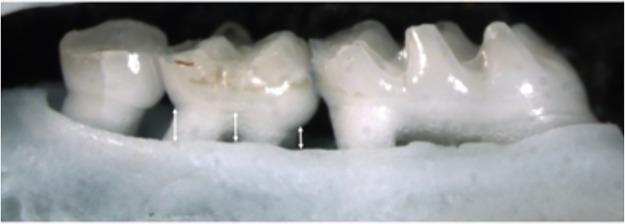

蔗糖和淀粉的摄入会导致自然发生牙周炎的啮齿动物模型中肺泡骨高度降低。

Sucrose and starch intake contribute to reduced alveolar bone height in a rodent model of naturally occurring periodontitis.

While there is a burgeoning interest in the effects of nutrition on systemic inflammatory diseases, how dietary macronutrient balance impacts local chronic inflammatory diseases in the mouth has been largely overlooked. Here, we used the Geometric Framework for Nutrition to test how the amounts of dietary macronutrients and their interactions, as well as carbohydrate type (starch vs sucrose vs resistant starch) influenced periodontitis-associated alveolar bone height in mice. Increasing intake of carbohydrates reduced alveolar bone height, while dietary protein had no effect. Whether carbohydrate came from sugar or starch did not influence the extent of alveolar bone height. In summary, the amount of carbohydrate in the diet modulated periodontitis-associated alveolar bone height independent of the source of carbohydrates.

摘要

虽然人们对营养对系统性炎症性疾病的影响越来越感兴趣,但饮食中宏量营养素的平衡如何影响口腔局部慢性炎症性疾病在很大程度上被忽视了。在这里,我们使用营养的几何框架来测试饮食中宏量营养素的量及其相互作用,以及碳水化合物的类型(淀粉与蔗糖与抗性淀粉)如何影响小鼠的牙周炎相关牙槽骨高度。增加碳水化合物的摄入会降低牙槽骨高度,而饮食中的蛋白质则没有影响。碳水化合物来自糖还是淀粉并不影响牙槽骨高度的程度。总之,饮食中碳水化合物的量调节了牙周炎相关的牙槽骨高度,而与碳水化合物的来源无关。